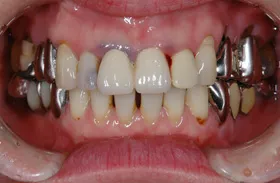

■治療前:奥歯が無いため噛み合わせが深く下の歯が全く見えない

噛み合わせが低いため全体的に歯が削れている

■治療後:下顎 左下5・6番、右下4・6番にインプラント治療

その他の歯に補綴治療をしたことにより、奥歯もしっかりと咬むことができ、奥歯ができたことにより噛み合わせも上がって下の歯も見えるようになり、審美的にも改善された

| 主訴 | 歯科治療をしても歯がすぐに欠けてしまう 奥歯が無いため、奥歯で咬めない |

| 治療方法 | インプラント治療 + 補綴治療 |

| 治療期間 | 約1年 |

| 通院回数等 | 約20回 |

| 費用 | 約250万円(税込) |

| リスク・副作用 | 術後の腫れ・痛み |